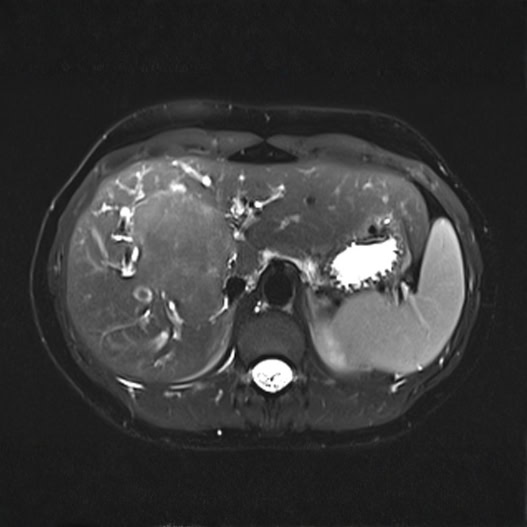

Conditions Detectable with Our Whole Body MRI

Whole Body Scan